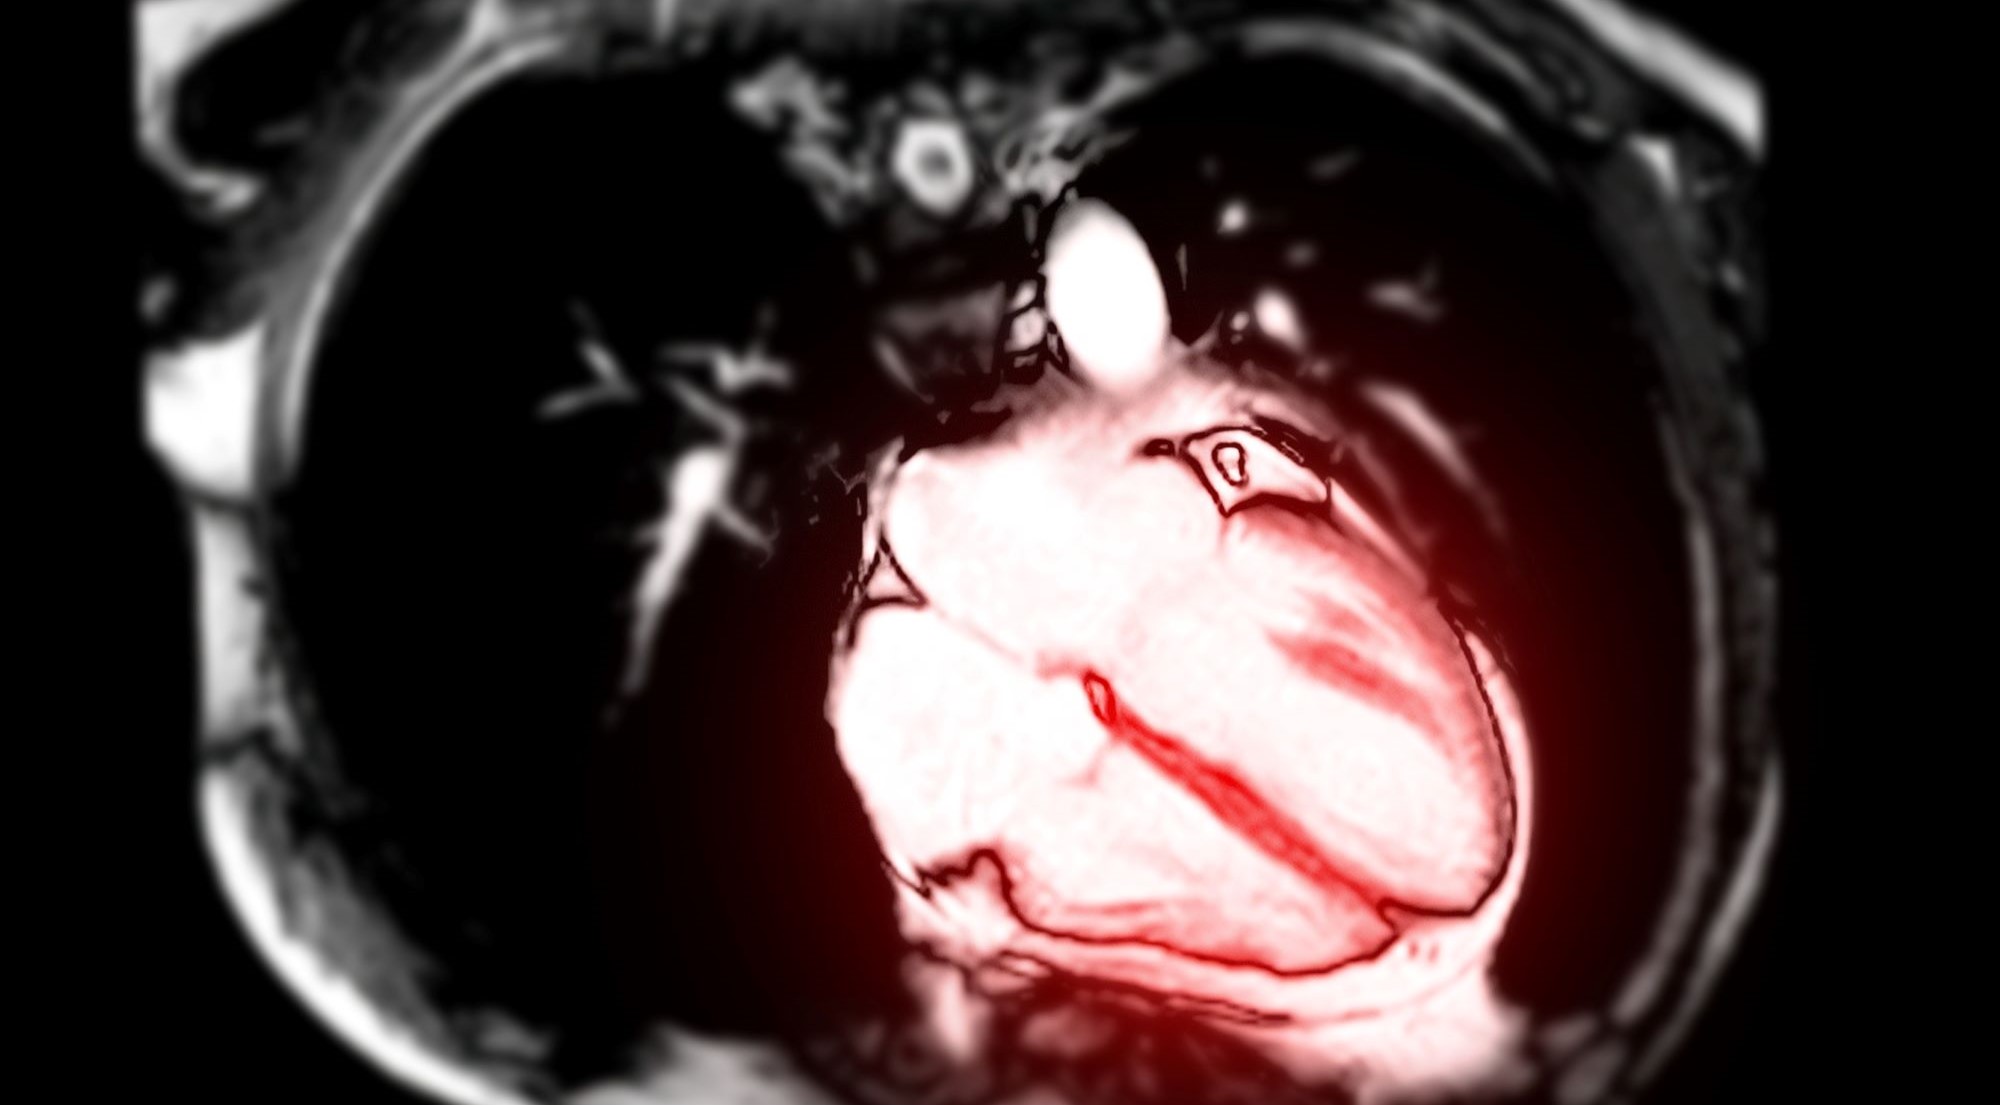

Myocarditis after COVID vaccines seen in MRI of heart

A heart viewed by MRI, one way to look for signs of myocarditis. Deposit Photos